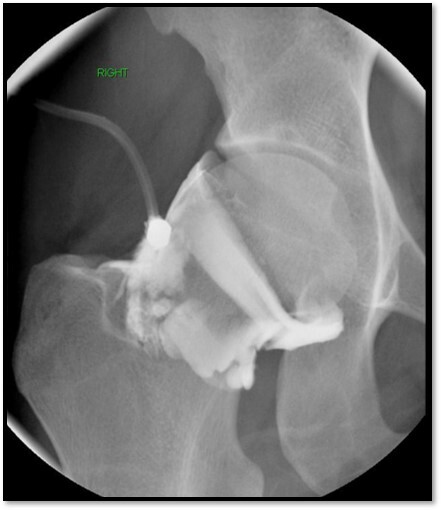

What process is this showing here?

A

Joint injection

Q